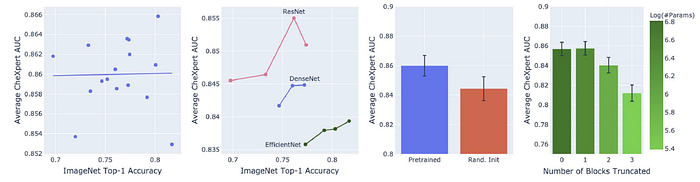

- Leftmost: Scatterplot and best-fit line for 16 pretrained models showing no relationship between ImageNet and CheXpert performance.

- Second Left: CheXpert performance relationship varies across architecture families much more than within.

- Second Right: Average CheXpert performance improves with pretraining.

- Rightmost: Models can maintain performance and improve parameter efficiency through truncation of final blocks.

There is no monotonic relationship between ImageNet and CheXpert performance without pretraining (Spearman 𝜌 = 0.08) or with pretraining (Spearman 𝜌 = 0.06).

- The logarithm of the model size has a near linear relationship with CheXpert performance when no pretraining (Spearman 𝜌 = 0.79).

- However once with pretraining, the monotonic relationship is weaker (Spearman 𝜌 = 0.56).

Most models benefit significantly from ImageNet pretraining. Smaller models tend to benefit more than larger models (Spearman 𝜌 = −0.72).

For all four model families, truncating the final block leads to no significant decrease in CheXpert AUC but can save 1.4× to 4.2× the parameters.